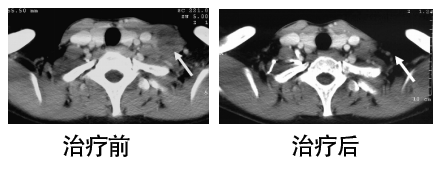

ACTL治疗案例